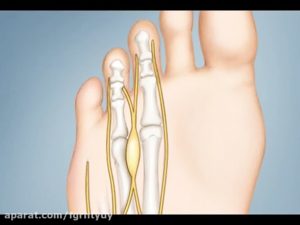

Неврома Мортона

При этом заболевании происходит разрастание ткани в стопе, которое зажимает межпальцевые нервы и приводит к болезненному состоянию. По сути, неврома представляет собой доброкачественную опухоль, характеризующуюся ощущением, будто в стопе находится камешек, который мешает ходить. Часто патология проявляется болью между пальцами на ноге, обычно между четвертым и третьим.

Факторами, предрасполагающими к появлению недуга, являются плоскостопие, травмы, нагрузка на стопы, тесная обувь.